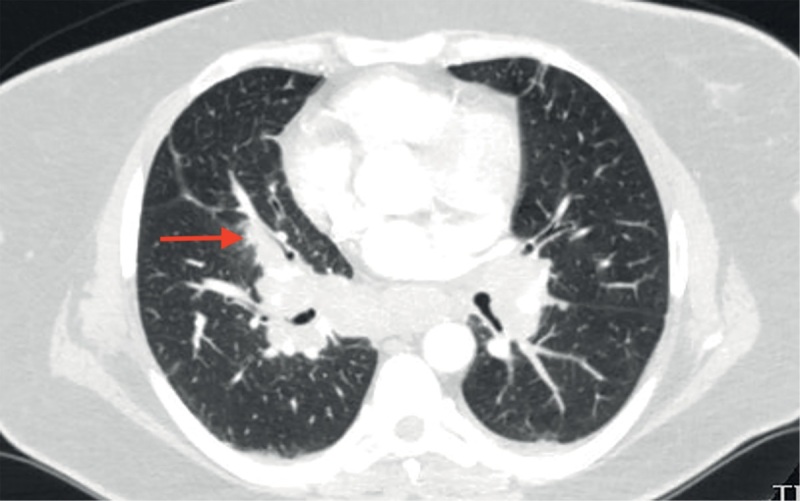

库欣病是一种罕见的严重神经内分泌疾病,由垂体肿瘤长期过度分泌促肾上腺皮质激素引起。内源性高皮质醇症患者体内皮质醇的生理浓度过高,具有类似于全身糖皮质激素治疗的免疫抑制和抗炎作用。这可能会降低患者并发的自身免疫性炎症疾病的活性。另一方面,在治疗库欣病的过程中,皮质醇水平的降低可能与免疫系统的重新激活有关,从而带来自身免疫性疾病发病或复发的风险。我们介绍了自己的一个临床病例,该病例显示,在对库欣病进行手术治疗后,出现了肉样瘤病。

Cushing's disease is a rare severe neuroendocrine disorder caused by chronic overproduction of adrenocorticotropic hormone by a pituitary tumor. Supraphysiological concentrations of cortisol in endogenous hypercortisolism have an immunosuppressive and anti-inflammatory effect similar to therapy with systemic glucocorticosteroids. This may reduce the activity of the patient's concomitant autoimmune inflammatory diseases. On the other hand, a decrease in cortisol levels during treatment for Cushing's disease may be associated with a reactivation of the immune system that pose a risk of onset or recurrence of an autoimmune disorder. We present our own clinical case demonstrating the development of sarcoidosis after surgical treatment of Cushing's disease.